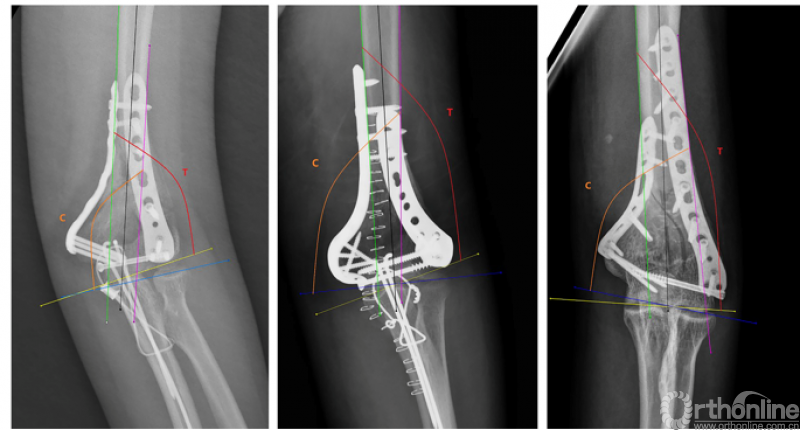

4、北京积水潭医院蒋协远教授等基于既往关于TCI(滑车肱骨小头指数)的研究做出改良并提出了modified TCI的测量方法,针对肱骨髁间骨折ORIF术后出现肘关节僵硬这一结局指标进行危险因素分析。研究发现,mTCI过大或过小均会导致术后肘关节僵硬的风险明显增加,并且高能量损伤以及受伤至手术时间超过1周同样是术后出现肘关节僵硬的独立危险因素。

1、肘关节旋转轴三维定位

国内蒋协远教授团队在世界上率先采用三维导航机器人进行肘关节旋转中心定位。TiRobot机器人导航辅助肘关节旋转中心轴定位能够极大地降低主观判断造成的旋转轴偏移,提高轴心定位精准度,减少反复透视验证的过度辐射及反复调整轴心导针的骨质破坏,避免可能的血管、神经损伤,显著减小降低术后肘关节活动阻力,并减少外固定针松动、断裂及外固定架断裂等并发症的发生率,从而整体提高治疗效果。